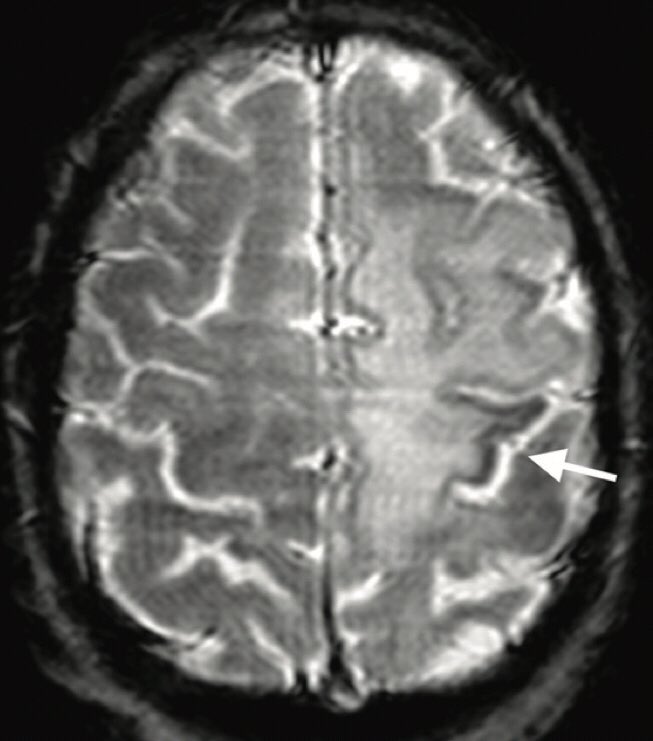

The rim is usually incomplete and signifies active infection Image

The Punctate Pattern (PP)

Refers to T2 weighted hyperintense or enhancing brain punctate lesions (milky way appearance)

The PP is a sensitive imaging feature of NTZ- PML and may be of use to differentiate PML lesions from MS plaques. ImageImage